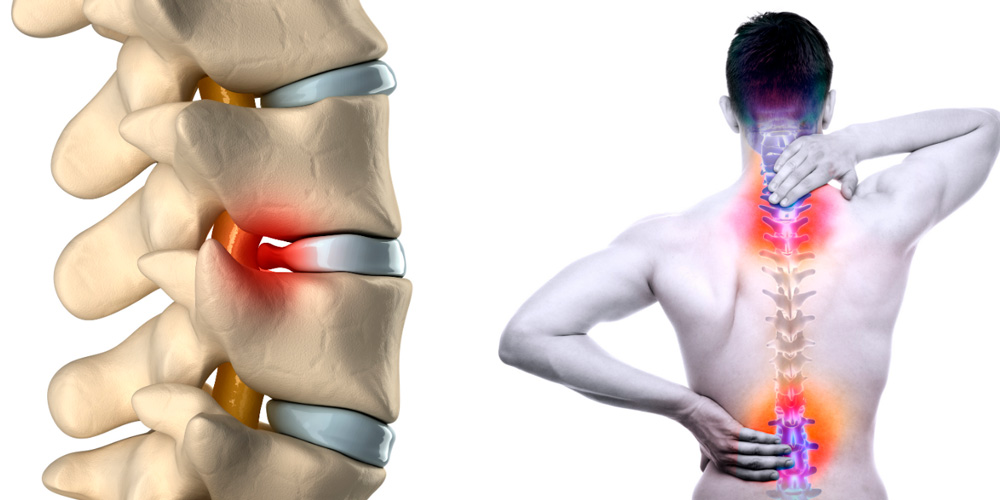

КТ-протрузии дисков: Визуализация и классификация